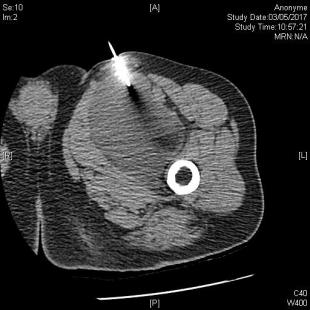

Le trajet de la biopsie, à anticiper

Les biopsies sont essentiellement faites par voie percutanée, leur taux de réponse en milieu spécialisé est de l’ordre de 95 % (méthode des réseaux du sarcome Netsarc). Les biopsies chirurgicales, plus rares, sont indiquées essentiellement pour des raisons techniques, ou lorsqu’il est impossible d’obtenir un résultat exploitable par microbiopsie. Qu’elle soit radioguidée ou chirurgicale, le trajet de la biopsie doit être décidé conjointement par le radiologue et le chirurgien car, en cas de réponse positive au diagnostic de sarcome, ce trajet devra être réséqué avec la lésion (figure 4).